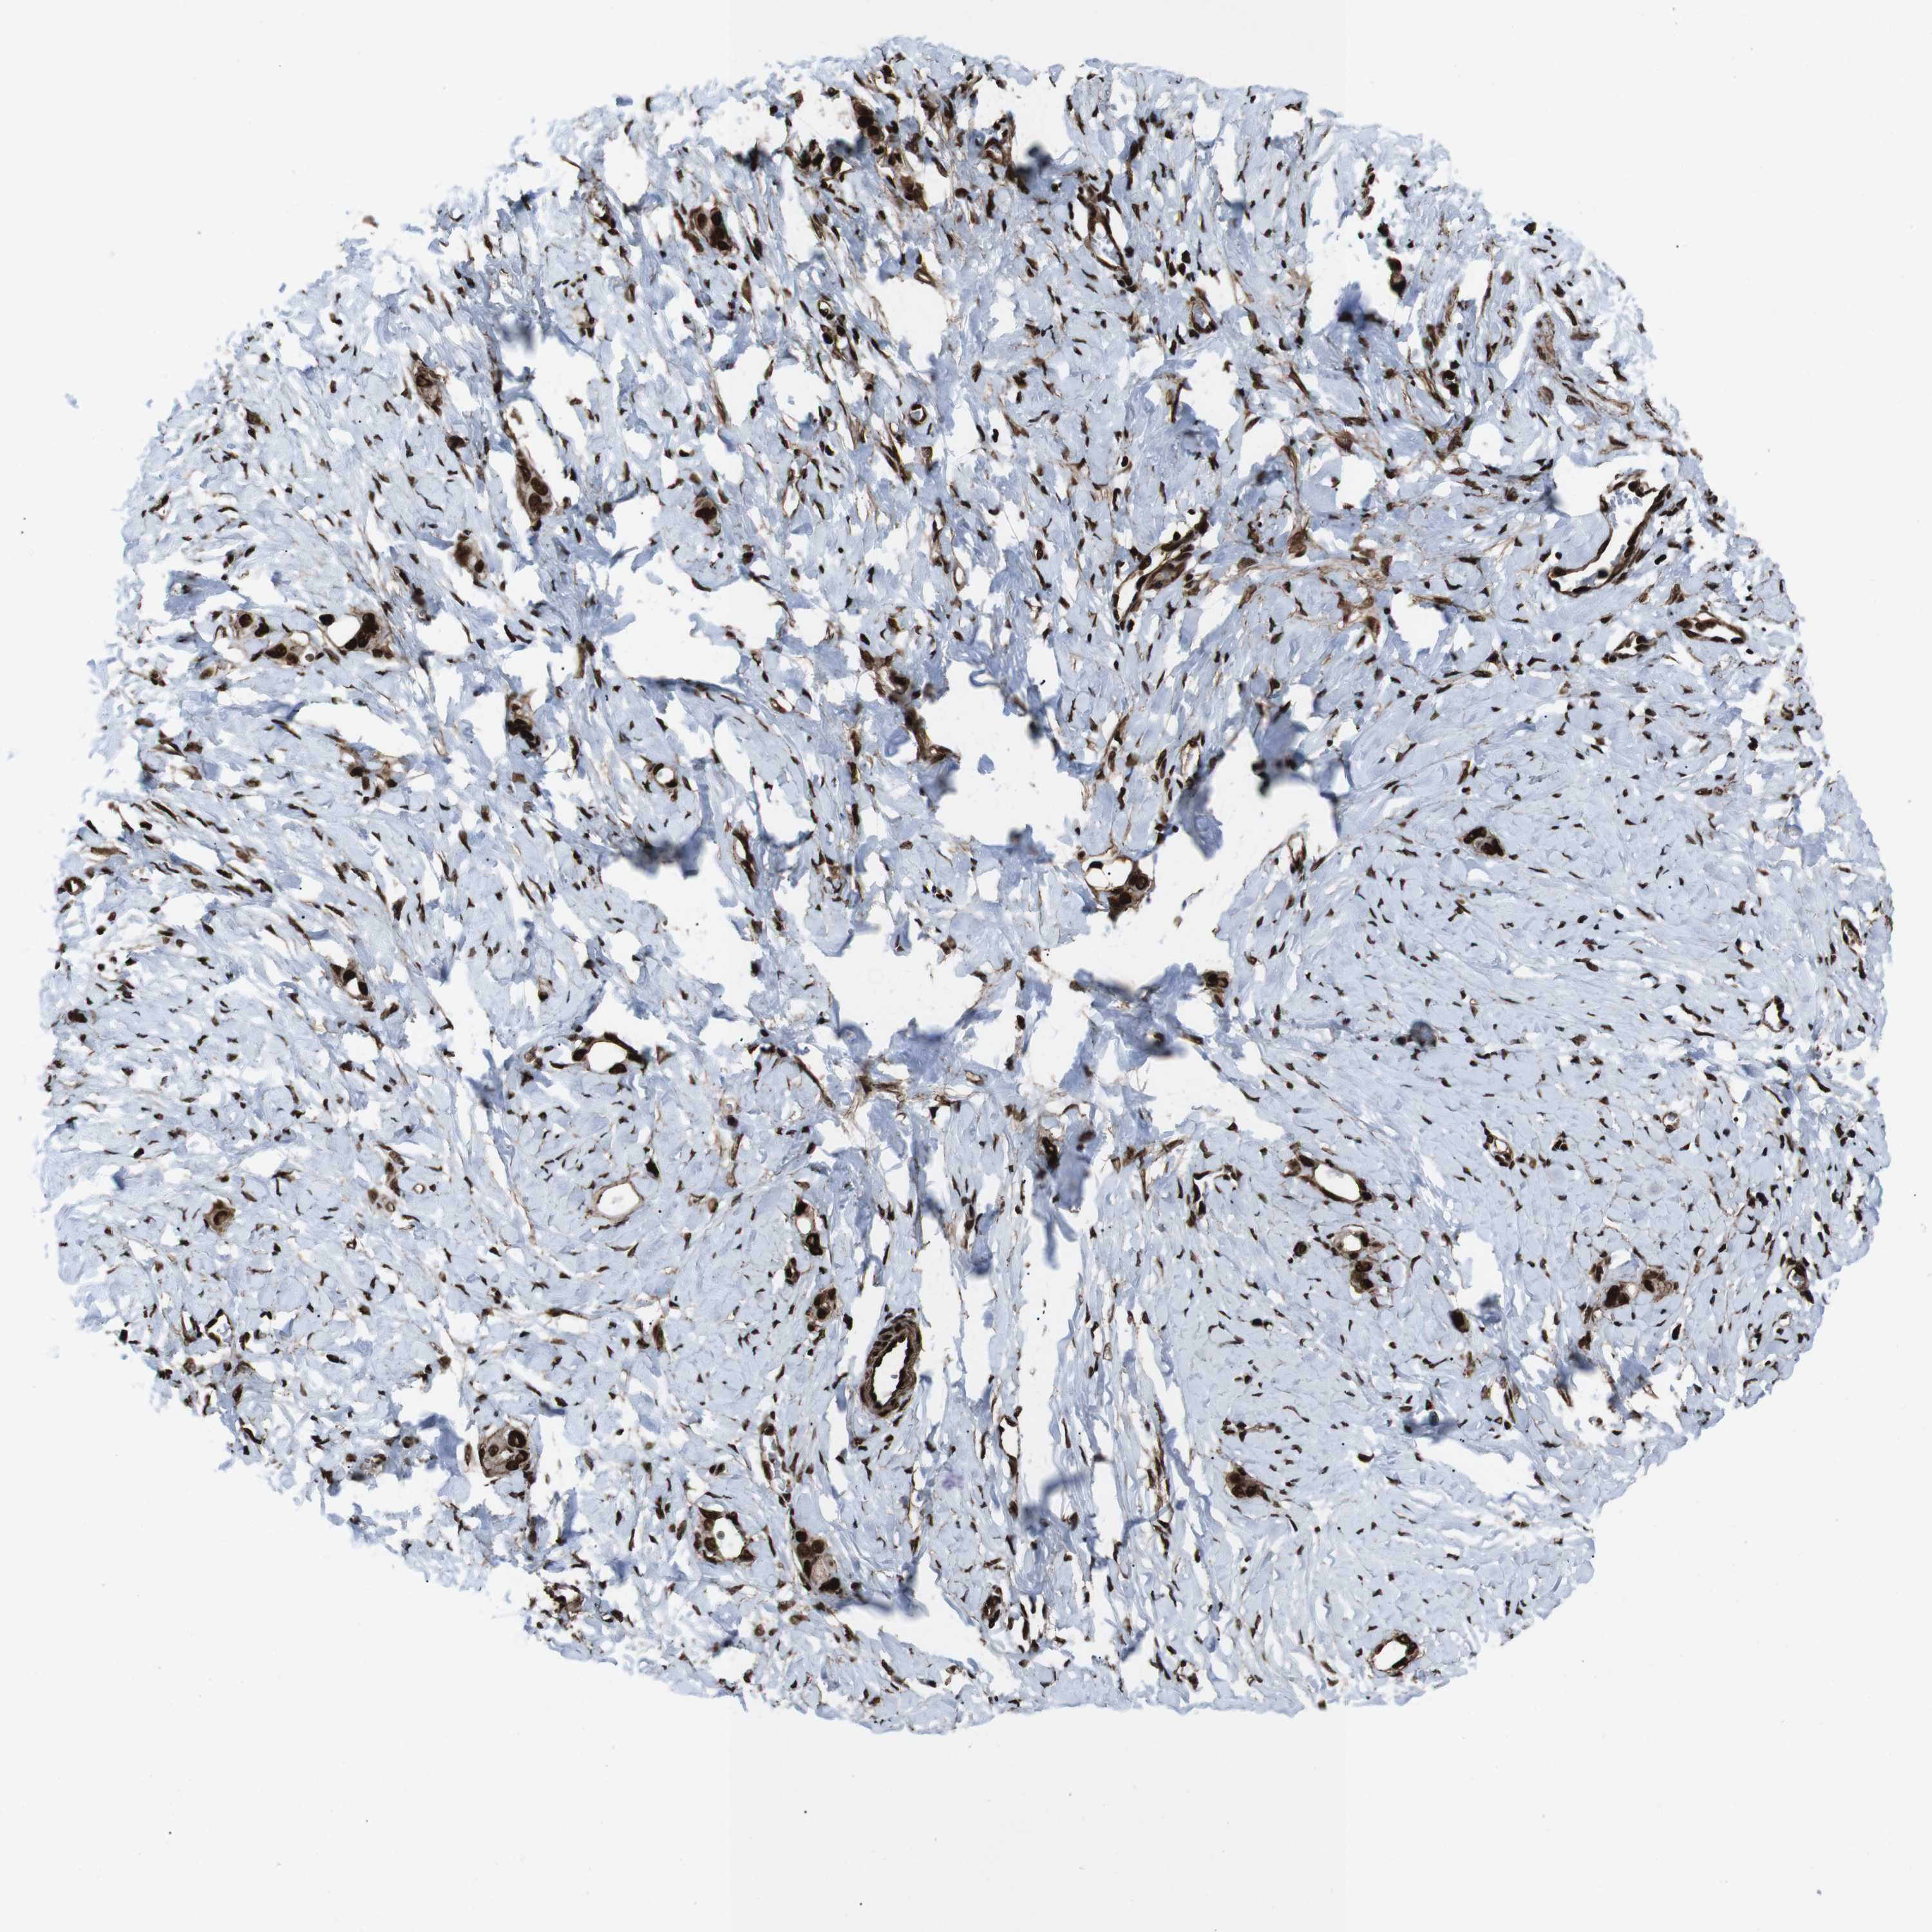

STOMACH CANCER - Protein expressioni

A mouse-over function shows sample information and annotation data. Click on an image to view it in a full screen mode. Samples can be filtered based on level of antibody staining by selecting one or several of the following categories: high, medium, low and not detected. The assay and annotation is described here.

Note that samples used for immunohistochemistry by the Human Protein Atlas do not correspond to samples in the TCGA dataset.

Antibody stainingi

Antibody staining in the annotated cell types in the current human tissue is reported as not detected, low, medium, or high, based on conventional immunohistochemistry profiling in selected tissues. This score is based on the combination of the staining intensity and fraction of stained cells.

Each image is clickable and will lead to virtual microscopy that enables deeper exploration of all samples and also displays staining intensity scores, fraction scores and subcellular localization as well as patient and tissue information for each sample.

Antibody HPA041057

Antibody HPA058707

Antibody CAB011532

Staining

High

Medium

Low

Not detected

Intensity

Strong

Moderate

Weak

Negative

Quantity

>75%

75%-25%

<25%

None

Location

Nuclear

Cytoplasmic/membranous

Cytoplasmic/membranous,nuclear

Adenocarcinoma, NOS

Adenocarcinoma, High grade